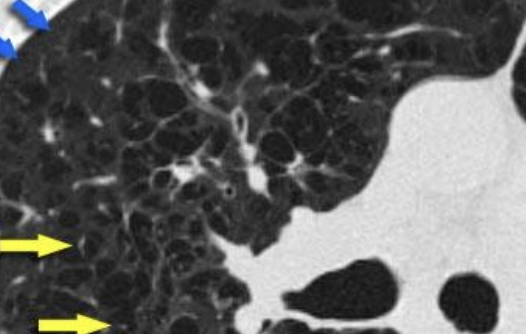

Paraseptal

Manguitos peribronquiales

Tranvía